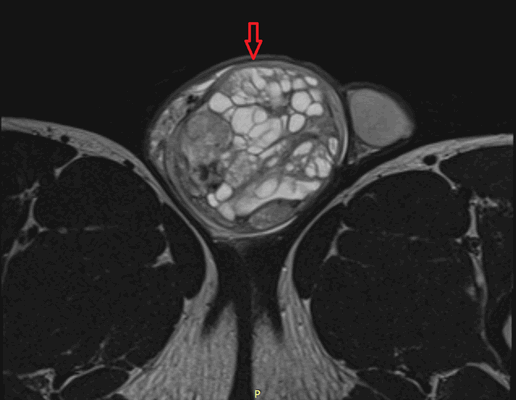

Рисунок 2. - семинома яичка: а — макропрепарат, б — МРТ.

Рисунок 3. - тератома яичника а -УЗИ, б — МРТ.